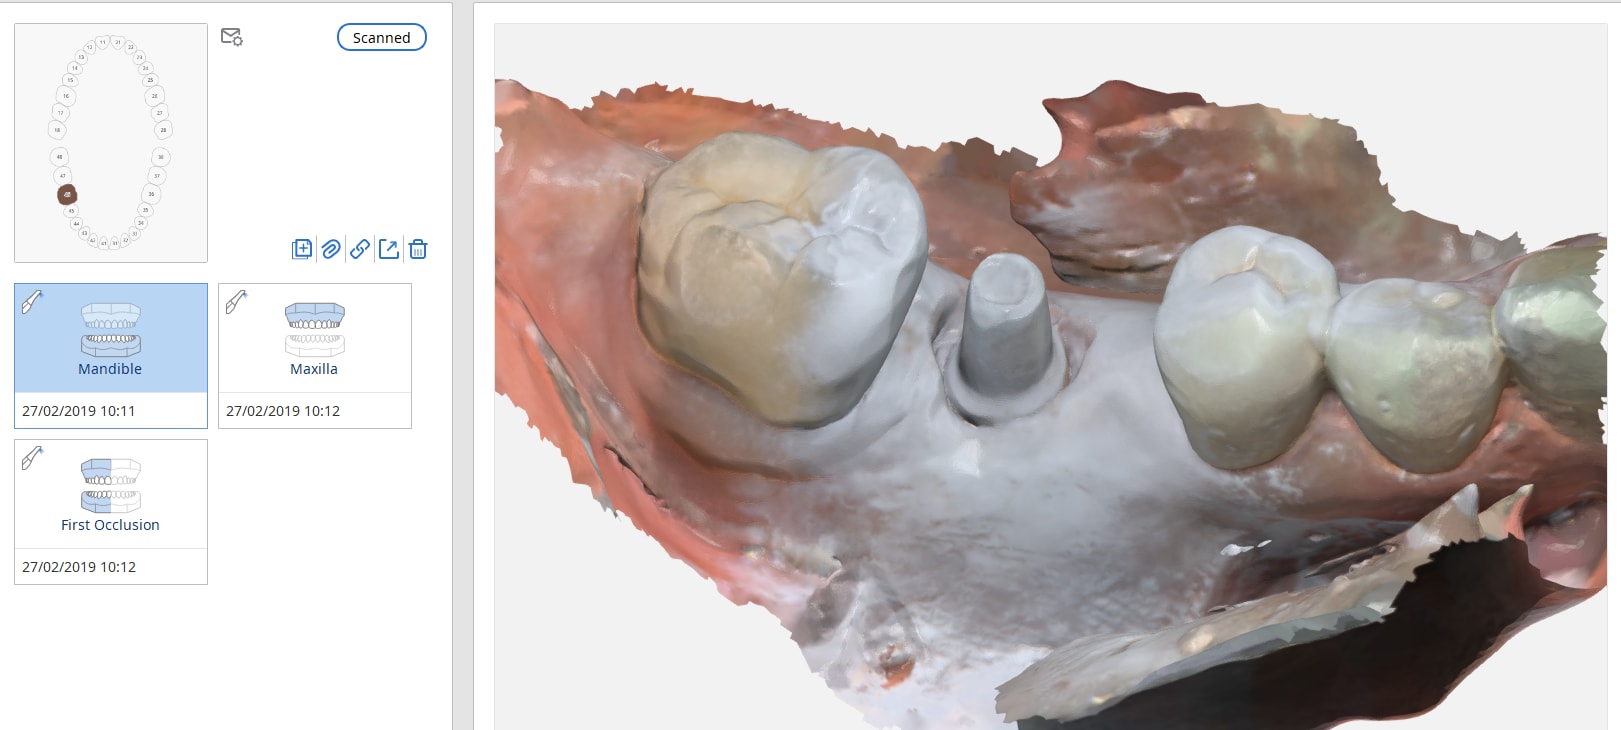

Bonsoir, lorsque l'on selectionne la bibliotheque d'implants dans le logiciel deconception du modele une logette propre à l'analogue est laissée dans le modèle imprimé, il reste à le glisser et à le claveter

Oui c'est très bien dit mais c'est dépendant système. Attention il faut que chaque système fournisse l'analogue et Le transfert correspondant avec la bonne bibliothèque.

Là cest un système type Zimmer (BRAT implant dans ce cas) connectique 3.5. Maintenant c'est aussi valable pour les implants direct etc... connectique 3.5 hexagone interne.